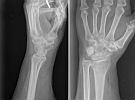

Pols